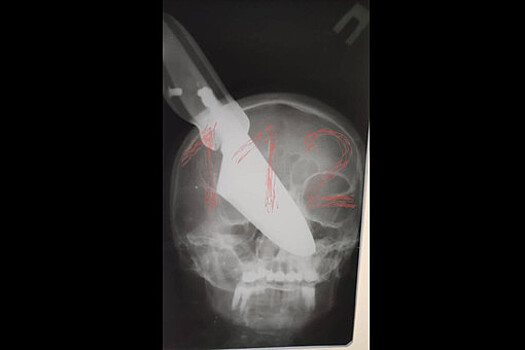

В городе Апшеронске Краснодарского края в ходе семейной ссоры мужчина воткнул нож в лицо своей супруги - женщина осталась жива, сообщается на сайте Следственного комитета по Кубани. Инцидент произошел вечером 19 ноября, когда 64-летний мужчина и 60-летняя женщина распивали спиртные напитки, находясь у себя дома. В ходе ссоры мужчина схватил нож и ударил свою жену ножом в область носа. Клинок застрял в лице женщины, которая сумела отбиться от мужа и выбежать на улицу, где позвала на помощь. "Местные жители вызвали на место бригаду скорой медицинской помощи и правоохранителей. Пострадавшая была доставлена в больницу, где ей продолжают оказывать медицинскую помощь", - указано в сообщении. Мужчина был задержан, ему предъявлено обвинение по ч. 3 статьи 30 и ч. 1 статьи 105 УК РФ в покушении на убийство. Ранее в Подмосковье пьяный сотрудник ГИБДД выстрелил в свою дочь в такси и сбежал.